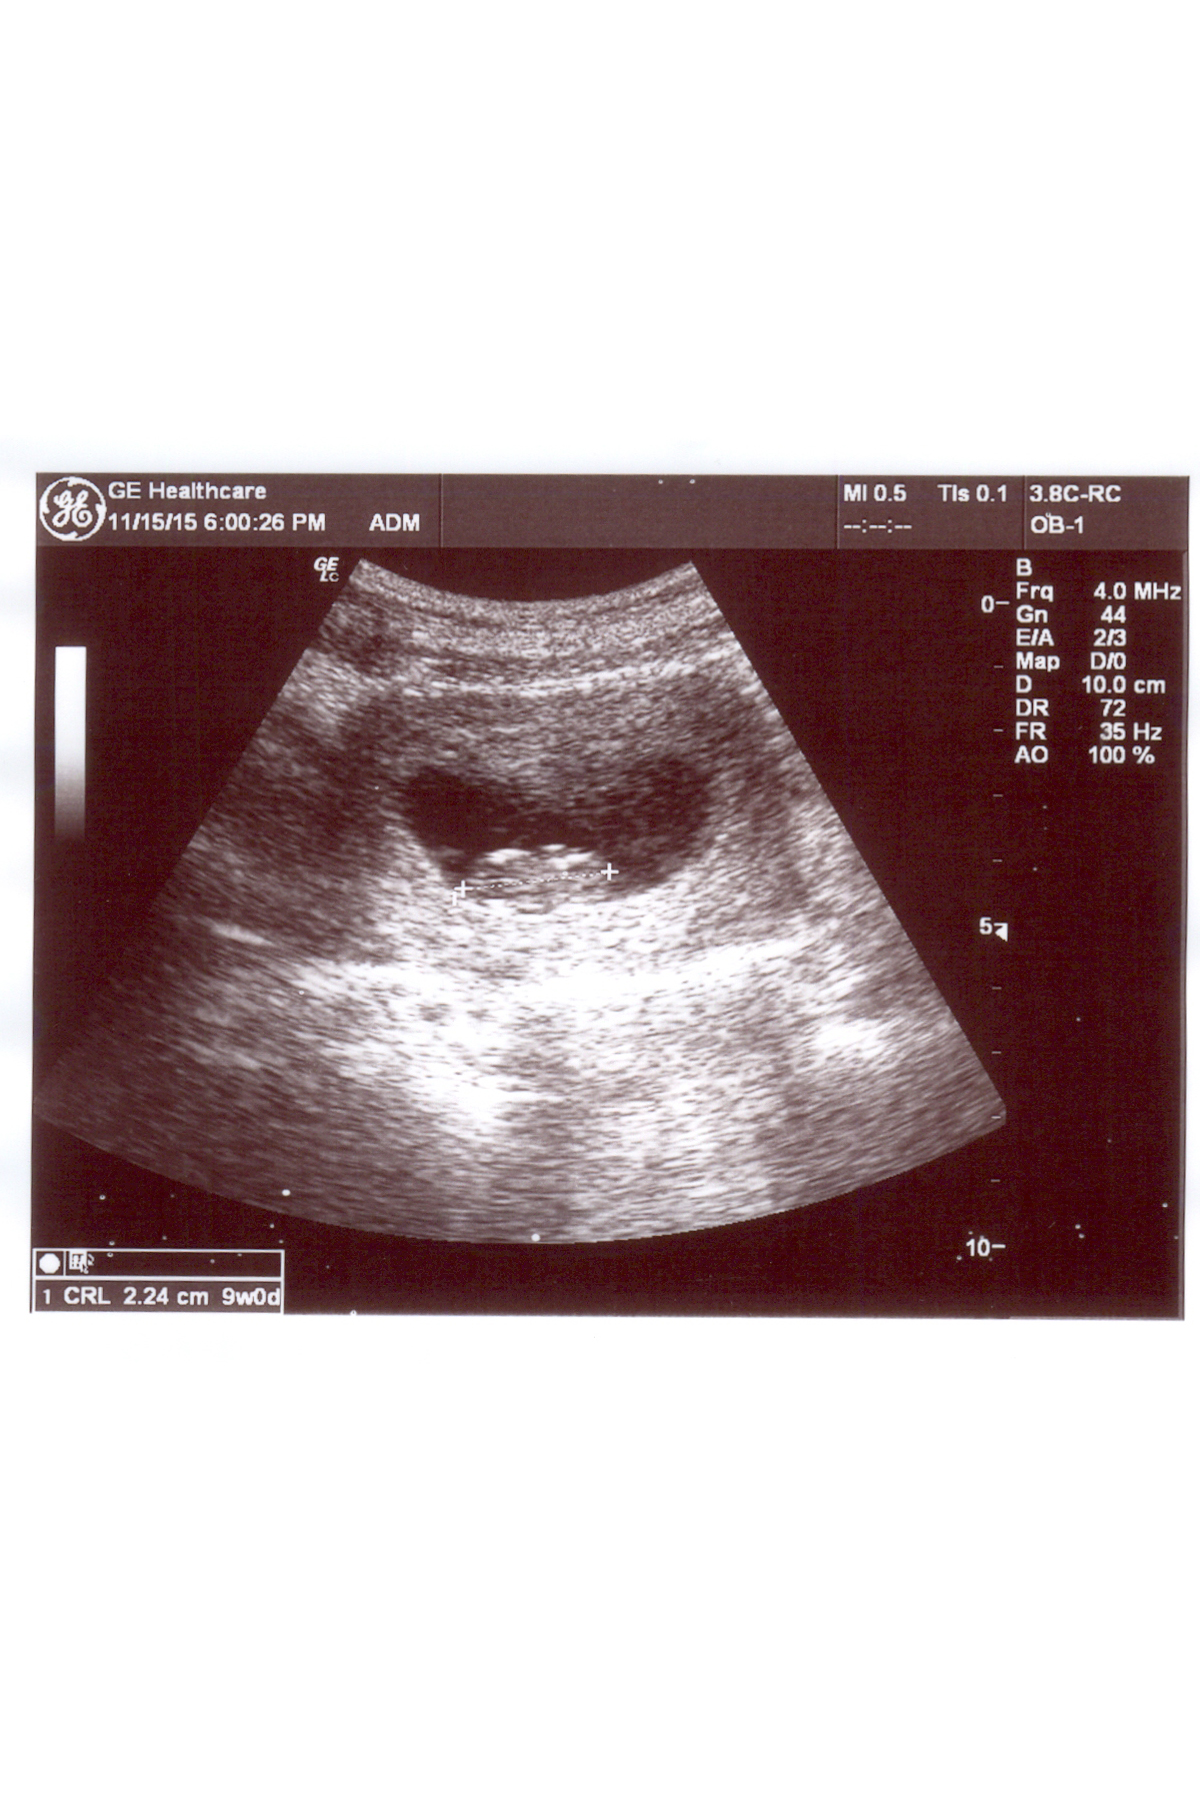

plz help me to predict my baby gender using ramzi theory or skull shape? this is 9week ul shot.Attachment 28596